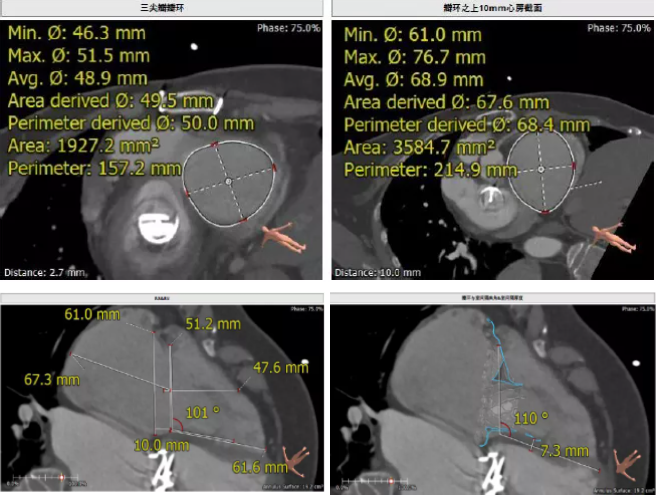

患者64歲女性,18年前接受了“正中開胸二尖瓣機械瓣置換術”,2年前超聲檢查發現“三尖瓣重度返流”。輾轉多地,嘗試各種治療方式,均無明顯改善。由于存在相關合并癥,傳統外科手術風險大,郭惠明教授團隊結合該患者CT、超聲檢查結果,對該患者的情況進行了充分的評估和討論,決定采用LuX-Valve人工三尖瓣介入瓣膜置換系統對患者進行微創介入治療,以最小的創傷解決患者的病痛。

術前CT評估